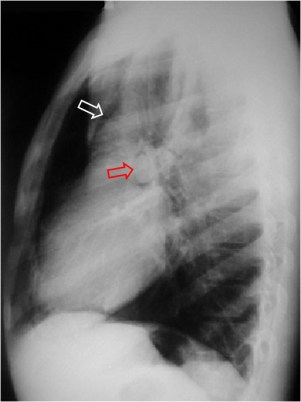

En la radiografía lateral de tórax puede verse la arteria pulmonar (flecha roja) rodeada de aire. También puede verse aire delimitando la raíz aórtica (flecha blanca).

Es un signo de neumomediastino visible en la radiografía lateral de tórax. El aire extrapulmonar rodea la porción mediastínica (extrapericardial) de la arteria pulmonar derecha produciendo un anillo hipodenso alrededor de ésta.